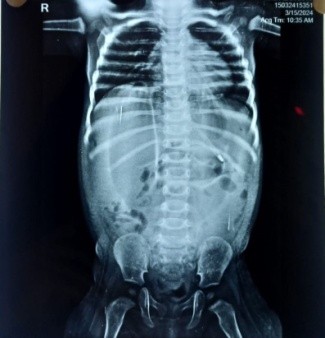

A previously healthy 1-year-old male baby was admitted with clinical signs of severe dehydration after 3 days of diarrhea, vomiting and fever. Upon admission he was lethargic and had clinical signs of shock with cold extremities, a prolonged capillary refill time (>3s) and tachycardia and abdominal distention. He was managed conservatively and advised X ray abdomen supine [Figure 1] which showed post diarrhoeal paralytic ileus with dilated bowel loops. Ultrasonography showed only mild fluid collection with internal septations. A plain abdominal x ray (erect) revealed free sub-diaphragmatic air [figure 2]. Suspecting intestinal perforation we decided to perform an exploratory laparotomy which revealed a small post-pyloric duodenal perforation [Figure 4]. Grahams patch repair was performed [Figure 5]. The postoperative course was uneventful [Figure 3]. Rotavirus antigen was found in feces.

Figure 2 Right Sided Sub Diaphragmatic Air Fluid Level

Figure 3 : X Ray Abdomen Erect Done Post Operatively Normal X ray Abdomen With Drains In Situ

Figure 2

Figure 3